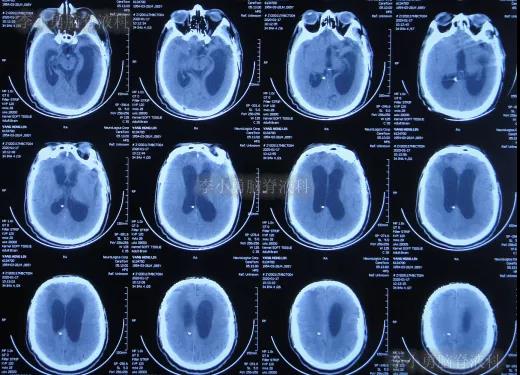

开颅术后第4天即2019年10月24日,查头颅CT示积血仍未明显减少(图-4)。

图-4:2019年10月24日头颅CT

继续治疗1周时间内,曾3次复查头颅CT(图-5、图-6、图-7)均示脑膨出逐渐加重的趋势,仍有积血;期间给予腰大池引流。

图-5:2019年10月26日头颅CT

图-6:2019年10月29日头颅CT

图-7:2019年10月31日头颅CT